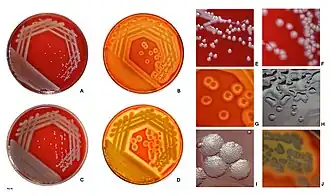

Identification of P. aeruginosa can be complicated by the fact individual isolates often lack motility. The colony morphology itself also displays several varieties. The main two types are large, smooth, with a flat edge and elevated center and small, rough, and convex.[88] A third type, mucoid, can also be found. The large colony can typically be found in clinal settings while the small is found in nature.[88] The third, however, is present in biological settings and has been found in respiratory and in the urinary tract.[88] Furthermore, mutations in the gene lasR drastically alter colony morphology and typically lead to failure to hydrolyze gelatin or hemolyze.

In certain conditions, P. aeruginosa can secrete a variety of pigments, including pyocyanin (blue), pyoverdine (yellow and fluorescent), pyorubin (red), and pyomelanin (brown). These can be used to identify the organism.[89]

Clinical identification of P. aeruginosa may include identifying the production of both pyocyanin and fluorescein, as well as its ability to grow at 42 °C. P. aeruginosa is capable of growth in diesel and jet fuels, where it is known as a hydrocarbon-using microorganism, causing microbial corrosion.[90] It creates dark, gellish mats sometimes improperly called "algae" because of their appearance.